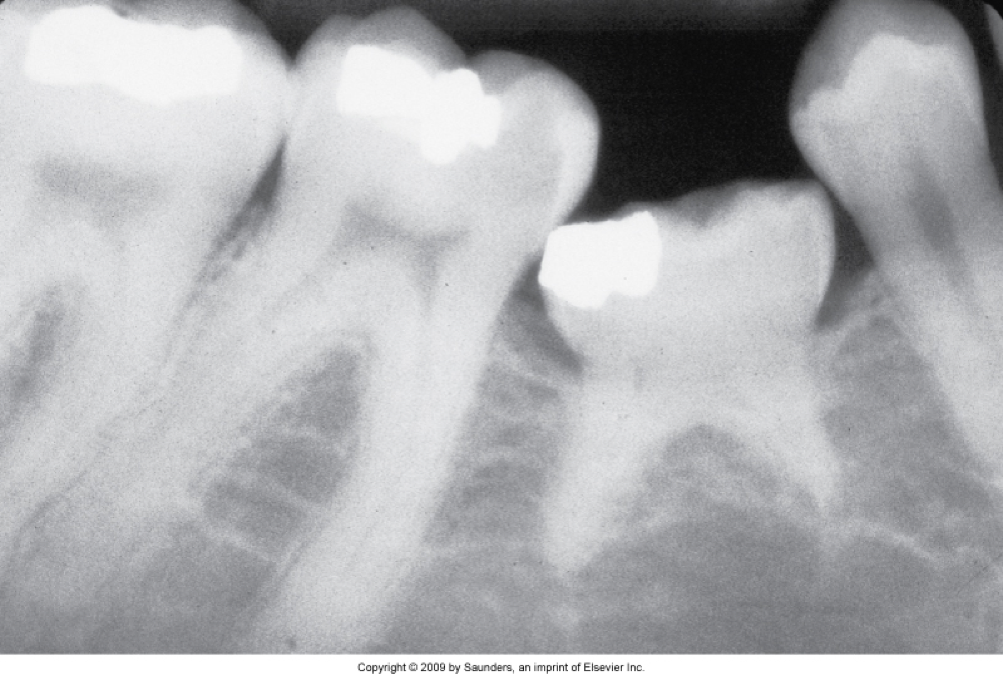

Dens in dente